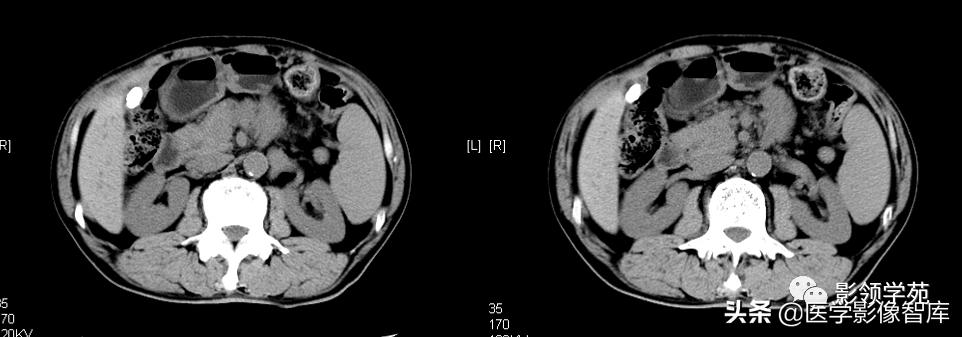

增强扫描:动脉期脾脏呈斑片状不均匀强化,静脉期及平衡期强化密度逐渐均匀。

1) 长径超过10cm,短径超过6cm,上下方向长度超过15cm即为脾肿大。

2) 横断面图像上以5个肋单元作为标准,超过者为脾肿大。若肝下缘消失的层面上,脾下缘仍能见到则可认为脾向下增大。

3) 当脾脏密度高于肝脏密度时,提示有肝脏弥漫性病变。